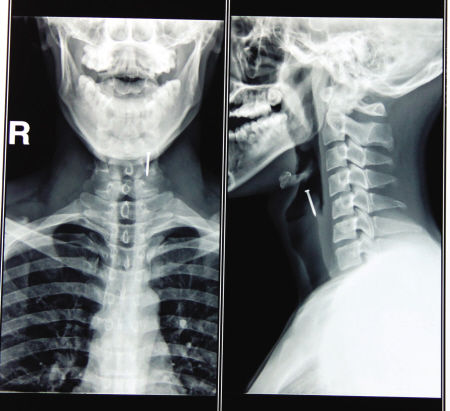

医院里,小刘大张着嘴,脖子僵硬不敢转动。由于钉子已经卡在喉咙里4个小时了,此时,他的脸色发白,头上渗着汗珠。五官科的关志华医生检查后发现,这根长约3厘米的铁钉,经过几番折腾,已经深深“钉”在了小刘的喉咽黏膜里,只剩一个螺帽裸露在外。

该如何救治?最终,关医生决定对小刘进行咽部局部麻醉,并用异物钳将钉子从其咽部顺利拔出。术后他对小刘进行再次检查,没有发现因为手术而损伤到周围的咽喉部。给其服用消炎药后,小刘就顺利出院了。

关医生说,幸亏小刘救治及时,否则可能导致食道被穿破,引起食管漏,一吃饭就呛;而更严重则会引起窒息,甚至因颈部血管破裂大出血死亡。关医生提示,异物误入食管后,一定要立即就医,以免增加并发症和手术困难。